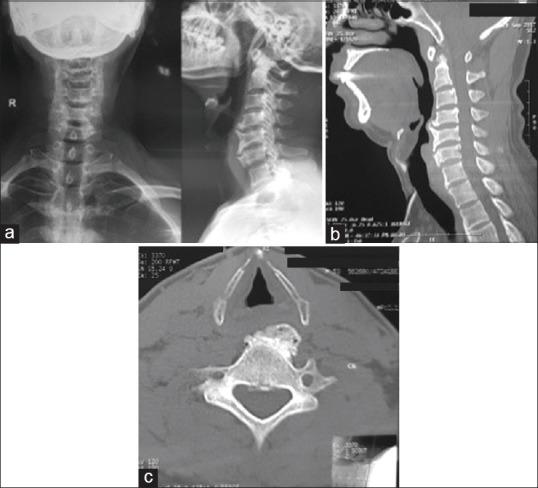

Cervical osteophytes may be seen in diffuse idiopathic skeletal hyperostosis, ankylosing spondylitis, posttraumatic, postoperative, degenerative causes, cervical spondylosis, and infectious spondylitis. A cervical osteophyte is very rarely considered among the differentials for symptoms of dysphagia. C5-C6 as well as C6-C7 being a site of greater load-bearing and mobility, the propensity to form osteophytes is high, with a small osteophyte leading to local mass effect. A 42-year-old male patient presented with mild dyspnea and significant dysphagia since 8 months, accompanied by dysphonia, weight loss, and intermittent aspiration. Clinical examination including neurological examination was normal. A barium swallow showed that osteophytes were severely protruding and displacing the lower pharynx and the proximal esophagus anterosuperiorly. The patient underwent surgical removal of the osteophyte through Smith-Robinson approach. Complaints of dysphagia were significantly decreased in postoperative period. A thorough evaluation is necessary to rule out other causes of dysphagia. Surgical management of this uncommon condition might be considered after confirmation of the osteophyte to be the offending lesion as it has favorable clinical outcomes.

颈椎骨赘可见于弥漫性特发性骨肥厚、强直性脊柱炎、创伤后、术后、退行性病因、颈椎病和感染性脊柱炎。在吞咽困难症状的鉴别诊断中,颈椎骨赘很少被考虑。C5-C6以及C6-C7是负重和活动度较大的部位,形成骨赘的倾向较高,小的骨赘会导致局部肿块效应。一名42岁男性患者自8个月以来出现轻度呼吸困难和明显的吞咽困难,伴有声音嘶哑、体重减轻和间歇性误吸。包括神经系统检查在内的临床检查均正常。吞钡检查显示骨赘严重突出并将下咽和食管近端向前上方推移。患者通过Smith-Robinson入路接受了骨赘切除术。术后吞咽困难的主诉明显减轻。有必要进行全面评估以排除吞咽困难的其他原因。在确认骨赘为致病病变后,可考虑对这种罕见情况进行手术治疗,因为其临床效果良好。